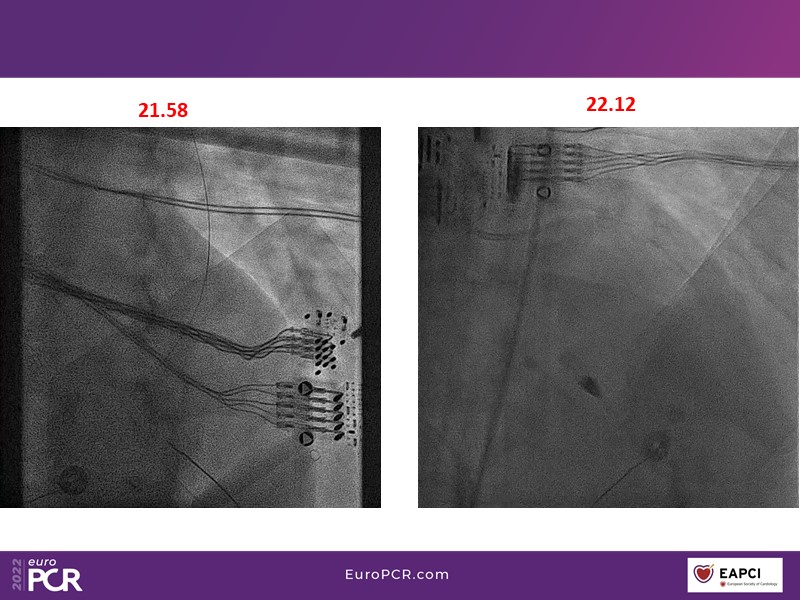

Tailored support for complex PCI and AMI with percutaneous mechanical circulatory support

Watch this EuroPCR 2022 session, in which Javier Escaned, Florim Cuculi, and Norman Mangner present different cases, to learn how standard operating procedures including mechanical circulatory support improve outcomes in patients with complex coronary lesions, discuss new strategies to overcome ischemic reperfusion lesions using percutaneous mechanical circulatory support, and understand the benefits of mechanical circulatory support in AMI patients.

- To learn how standard operating procedures including mechanical circulatory support improve outcome in patients with complex coronary lesions